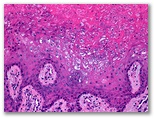

Granuloma piogenico

Diagnostico